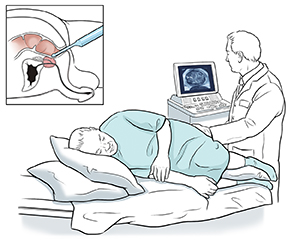

You'll be asked to change into a hospital gown. You'll then lie on your side with your knees bent up toward your chest.

The test is done with a hand-held ultrasound probe. A disposable cover is put on the probe. The probe is a tube-shaped rod about the size of a finger. A gel is put on the probe to grease (lubricate) it.

Your healthcare provider gently puts the probe into your rectum. You'll feel pressure, but if it hurts, let your provider know.

Sound waves are sent into the probe and through the wall of your rectum. They bounce off your prostate. A computer uses them to form an image of the gland and nearby tissues.

Your provider looks at the image and checks the size and shape of your prostate.